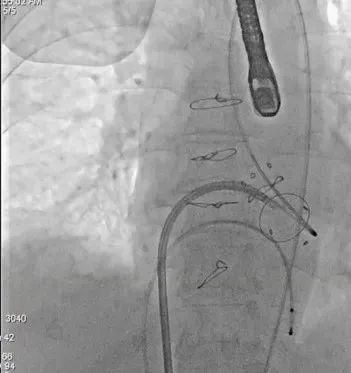

经房间隔二尖瓣跨瓣后,抓捕器在升主动脉抓捕J头泥鳅建立体外化轨道

动脉系统送入7F guiding,将guiding套在JR4导管里面,完成整体导管通路的建立

导管轨道交换Astato 300cm 导丝,确认轨道导丝体外化

将JR4与guiding脱离,guiding头端留在心室,JR导管撤回Agilis可调弯鞘管内

确认Lampoon技术成功后,保留全轨情况下二尖瓣环内放入超硬导丝至左心室

应用14mm球囊充分扩张房间隔

送入23mm SAPIEN 3瓣膜

DSA引导下调整瓣膜位置

快速起搏180次/分,23mm+2cc球囊膨胀扩张瓣膜

左室造影显示无PVL